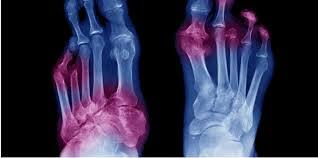

痛風是一種全身性疾病,由尿酸單鈉晶體(MSU)沉積在組織中引起。血清尿酸(SUA)高於特定閾值是形成尿酸晶體的必要條件。儘管高尿酸血症是痛風的主要致病缺陷,但許多高尿酸血症患者並沒有發展成痛風,甚至沒有形成尿酸結晶。事實上,只有5%的高尿酸血症超過9毫克/分昇的人會患痛風。因此,有人認為遺傳傾向等其他因素也參與了痛風的發病。

尿酸單鈉晶體可以沉積在所有組織中,主要是在形成tophi的關節及其周圍。痛風的診斷主要是通過關節液體抽吸或tophi抽吸來鑒別病理性MSU晶體。痛風的早期表現是急性關節炎症,可通過非甾體抗炎藥或秋水仙堿迅速緩解。腎結石和腎結石是晚期表現。通過飲食調整和使用降低血尿酸的藥物來降低SUA水准低於沉積閾值是痛風治療的主要目標。這導致MSU晶體溶解,防止進一步攻擊。

Gout is a systemic disease that results from the deposition of monosodium urate crystals (MSU) in tissues. Increased serum uric acid (SUA) above a specific threshold is a requirement for the formation of uric acid crystals. Despite the fact that hyperuricemia is the main pathogenic defect in gout, many people with hyperuricemia do not develop gout or even form UA crystals. In fact, only 5% of people with hyperuriceamia above 9 mg/dL develop gout. Accordingly, it is thought that other factors such as genetic predisposition share in the incidence of gout.

Monosodium urate crystals crystals can be deposited in all tissues mainly in and around the joints forming tophi. Gout is mainly diagnosed by identification of the pathognomonic MSU crystals by joint fluid aspiration or in tophi aspirate. Early presentation of gout is an acute joint inflammation that is quickly relieved by NSAIDs or colchicine. Renal stones and tophi are late presentations. Lowering SUA levels below deposition threshold either by dietary modification and using serum uric acid lowering drugs is the main goal in management of gout. This results in dissolution of MSU crystals preventing further attack.